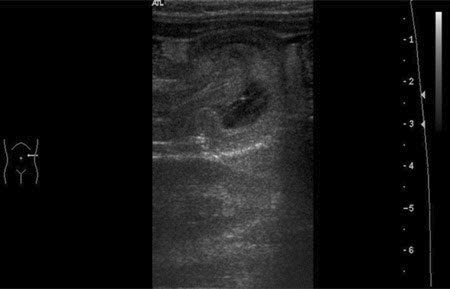

Intussuscepção: imagem de ultrassonografia que mostra a invaginação de um segmento do intestino no segmento adjacente

BMJ Case Reports 2009; doi:10.1136/bcr.04.2009.1730